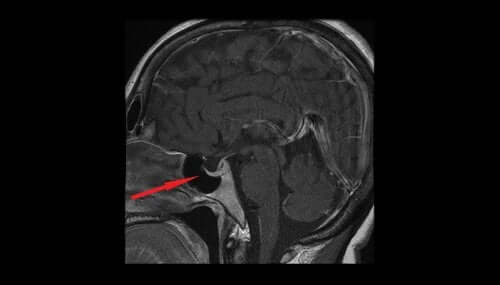

Les examens les plus pertinents qui aident à confirmer le diagnostic sont celui du champ visuel, la Tomodensitométrie Cérébrale et l’IRM cérébrale.